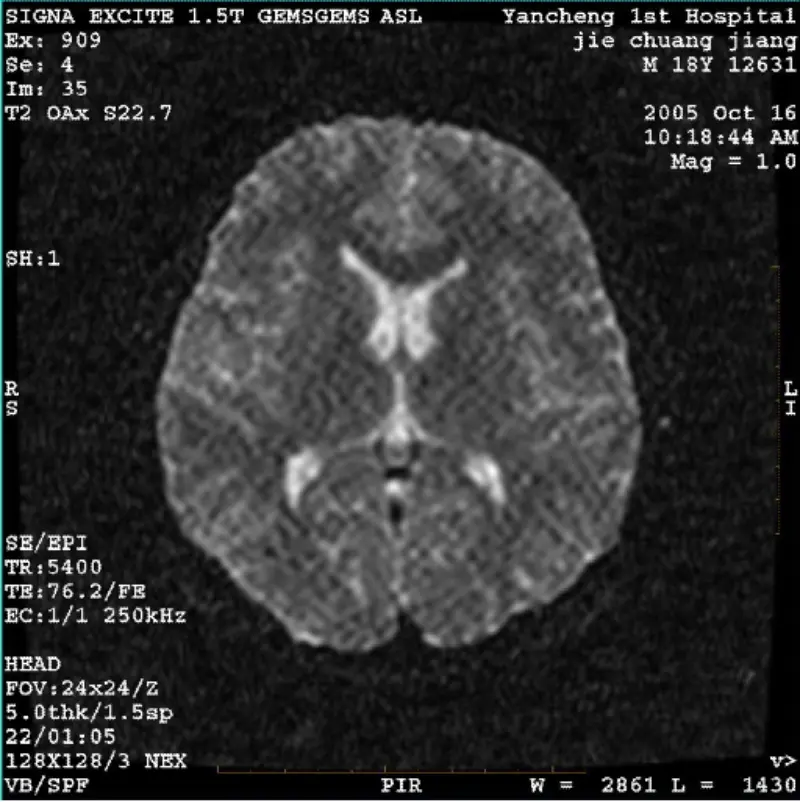

Lees verderSYSTEEM: 1.5T Signa Twin Excite II (softwareversie 11.0M4) PROBLEEM/SYMPTOEN DWI (zoommodus en hele modus) en fiesta (zoommodus en hele modus) afbeelding hebben zichtbaar reticulair of corduroy artefact, ongeacht bij gebruik van lichaamsspoel of hoofd spoel, ander routinebeeld lijkt normaal